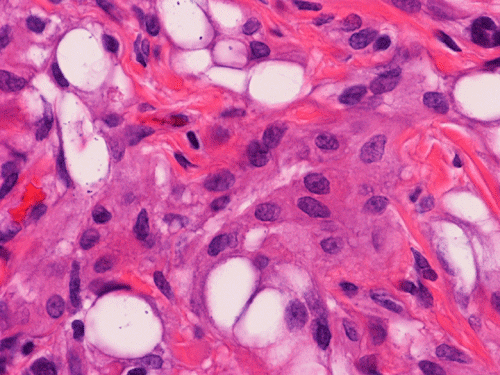

On scanning magnification, there is a round lesion in tissue around the fallopian tube (arrows in Panel A). The lesion does not invade into the tube nor distort or compress the tube. The cross sectional dimension is about the same diameter of the fallopian tube. On low and medium magnification, the lesion is composed of a collection of small microcysts intermingled with the smooth muscle bundles of the wall of the fallopian tube (Panel B and C). On higher magnification, the cyst or gland like spaces are lined by epithelioid to spindle cells with bland nuclei and an abundant amount of amphophilic cytoplasm (Panel D and E). The spindle cells are positive for calretinin, cytokeratin 5/6, and inhibin (Panel F, G, and H).

Histologically, the salient feature is small, microcystic or gland-like cystic spaces lined by flattened cells. Some of the tumor cells may arrange in cords and tubules.  Hyaluronic acid rich material that can be easily demonstrated by Alcian blue stain are present in the small glands and cysts. The tumor cells are medium in size and contain moderate to abundant amphophilic to eosinophilic cytoplasm. Prominent cytoplasmic vacuoles that suggest signet ring cells may be present. This is an important feature to know in order not to confuse these tumors with primary and metastatic carcinomas particularly when the specimen is obtained from the ovary. Although these tumor appears well-circumscribed on gross examination, these tumor appears infiltrative on microscopically and should not be confused with adenocarcinoma. The key to avoid this pitfall is that adenomatoid tumor have bland nuclear feature and no mitotic figures. Infaction can occur in adenomatoid tumor.